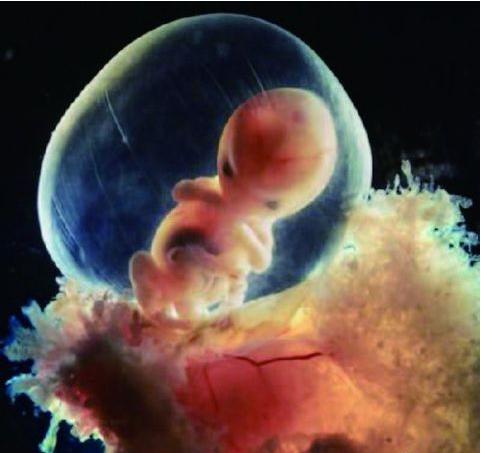

3、胎芽(FE)

早期胎儿。B超在怀孕6~7周可见胎芽。